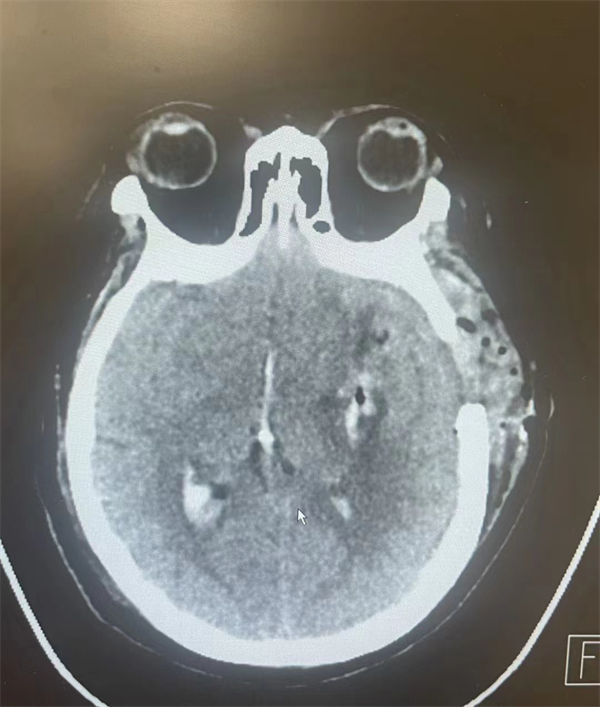

整個手術(shù)過程非常順利,術(shù)后穆阿姨意識逐漸轉(zhuǎn)為清醒,復(fù)查頭顱CT血腫已經(jīng)完全清除。

手術(shù)后